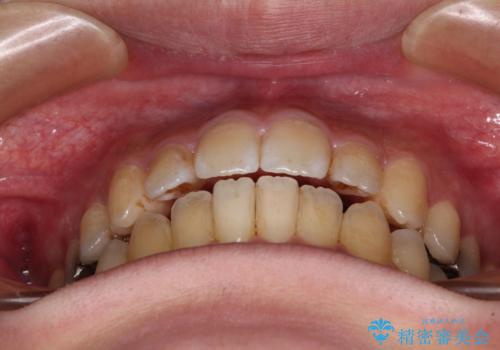

オープンバイトと目立つ銀歯 インビザライン矯正とセラミック修復治療

- 奥歯の目立つ銀歯と上下前歯の叢生と隙間を気にして来院された患者様です。

開咬の治療は、前歯を閉じるように動かすとともに、上下臼歯を圧下(骨内にめり込ませる)させることで進めて行きます。

銀歯については、矯正治療により咬合関係を改善し、矯正治療後半に修復治療を行うこととしました。

修復治療後に細かい部分をインビザラインで再度仕上げるプランとしました。